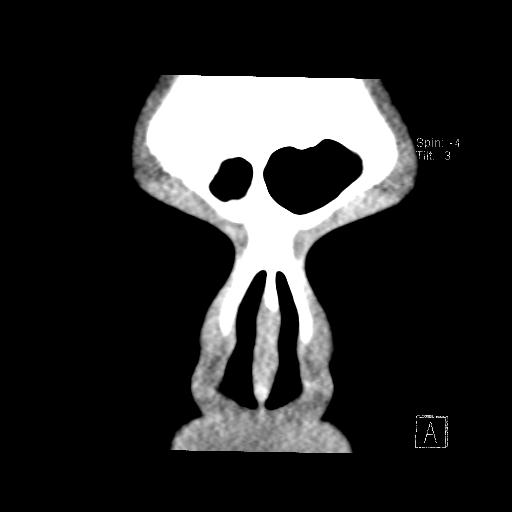

All three issues are visible in the following high-contrast image:

Here is roughly the same slice at a different contrast in which bone and soft tissue are more distinguishable:

Let’s take the three issues separately…